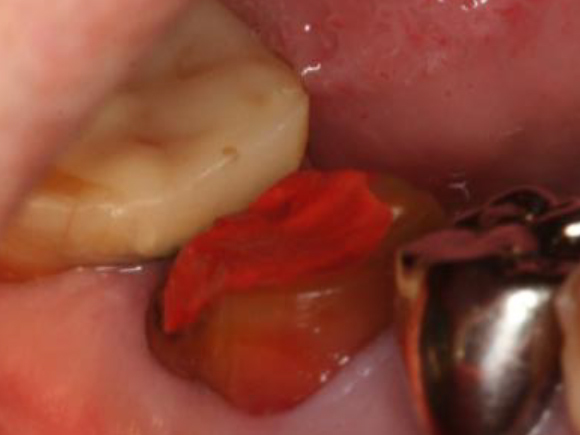

歯周外科処置

浜松市中区の症例紹介 歯周外科

歯周外科処置後

再生療法を行なった処置

Before

After

初診時年齢:30代女性

治療:歯周病治療

治療法:歯周組織再生療法

治療期間:1ヶ月

費用:110,000円(税込)

リスク・副作用:歯周外科処置後に出血、腫れ、あざが出ることがありますが時間とともに治ります。術後3週間程度噛んだときの痛みや歯が浮いた感じがすることがあります。